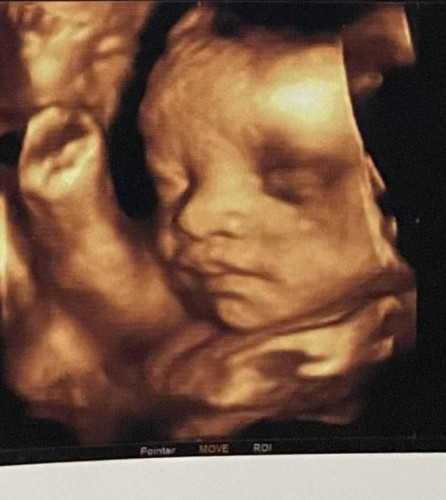

เมื่อวาน 30Weeks อัลตร้าซาวด์แบบ 4D มาค่ะ น้ำหนัก 1,536 g. ท้องแรกค่ะ 😁 #ท้องแรก

ทีมมีนา66ค่ะ แต่ฤกษ์ผ่า27Feb รูปนี้ตอนอายุครรภ์ 30w (ปัจจุบัน33w+2)

กำหนดคลอดมีนาคม รูปนี้29+3วีค น้องหนัก2,000g ลูกชายค่ะ ❤️☺️

ซาวด์ตอน29+2ค่ะ ในรูปน้อง1606 ท้อง2น้องผู้ชาย กำหนด20มีนาค่ะ

บ้านนี้ซาวด์ตอน30w. เหมือนกันค่ะ 1,600g ค่ะ ตอนนี้32แล้วค่ะ🥰